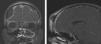

Niño de 8 años con fiebre de 72 h de evolución, acompañada de cefalea frontal y varios vómitos no proyectivos. A la exploración, únicamente destacaba un bultoma centrofrontal, que la familia relacionaba con traumatismo leve 2 días antes del inicio de la fiebre. No mucosidad nasal ni tos los días previos. La analítica sanguínea mostraba leucocitosis discreta (15.900 leucocitos/mm3, 60% neutrófilos) y proteína C reactiva (PCR) de 3,11mg/dl. Se decide ingreso en observación ante la preocupación familiar por la cefalea y la fiebre. A las 48 h del ingreso, el bultoma frontal era muy llamativo (fig. 1), con cierta fluctuación y muy doloroso, aunque el estado general del niño era bueno, sin clínica neurológica. La analítica sanguínea en ese momento mostraba una PCR de 7,43mg/dl, con 13.500 leucocitos/mm3 (55% neutrófilos). La ecografía confirmó la sospecha de absceso subperióstico, apreciándose una posible extensión intracraneal, practicándose una resonancia magnética craneal. Esta mostró un empiema epidural frontal bilateral (fig. 2). Se comenzó entonces tratamiento por vía intravenosa con amoxicilina-clavulánico y Neurocirugía realizó drenaje de la colecciones epidurales y subperióstica 24 h más tarde. La evolución fue muy satisfactoria, siendo alta a los 10 días de la intervención, sin problemas posteriores.